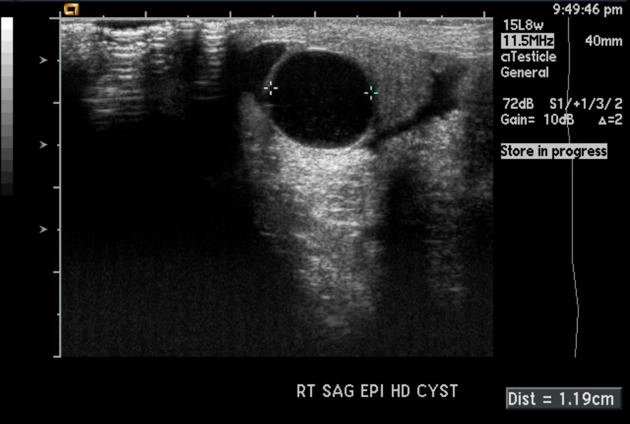

Nang mào tinh (Epididymal cyst)

16/03/2026